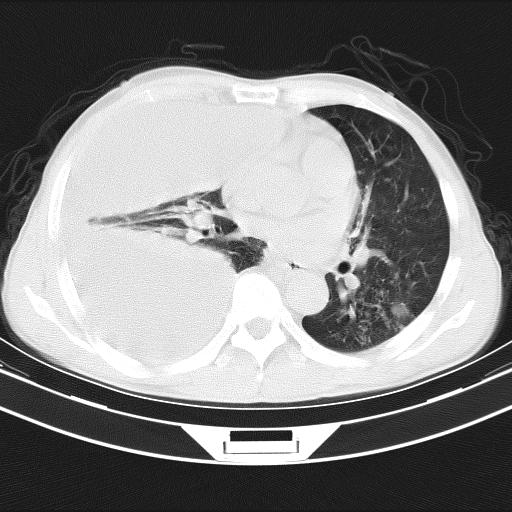

男性,44岁,结核病史多年。现胸闷气短,咳嗽,偶咳血。

右侧胸腔积液

右肺下叶不张

双肺多发结节影最分空洞形成考虑占位不除外结核

双肺陈旧性病变

1、右侧大量胸腔积液伴右肺压缩性膨胀不全,建议抽液治疗后复查 2、两肺继发性tb伴空洞形成。

1)两肺继发性肺结核伴空洞形成,左肺多发性结核球。2)右侧大量胸腔积液伴右肺部分膨胀不全。3)纵隔淋巴结肿大。